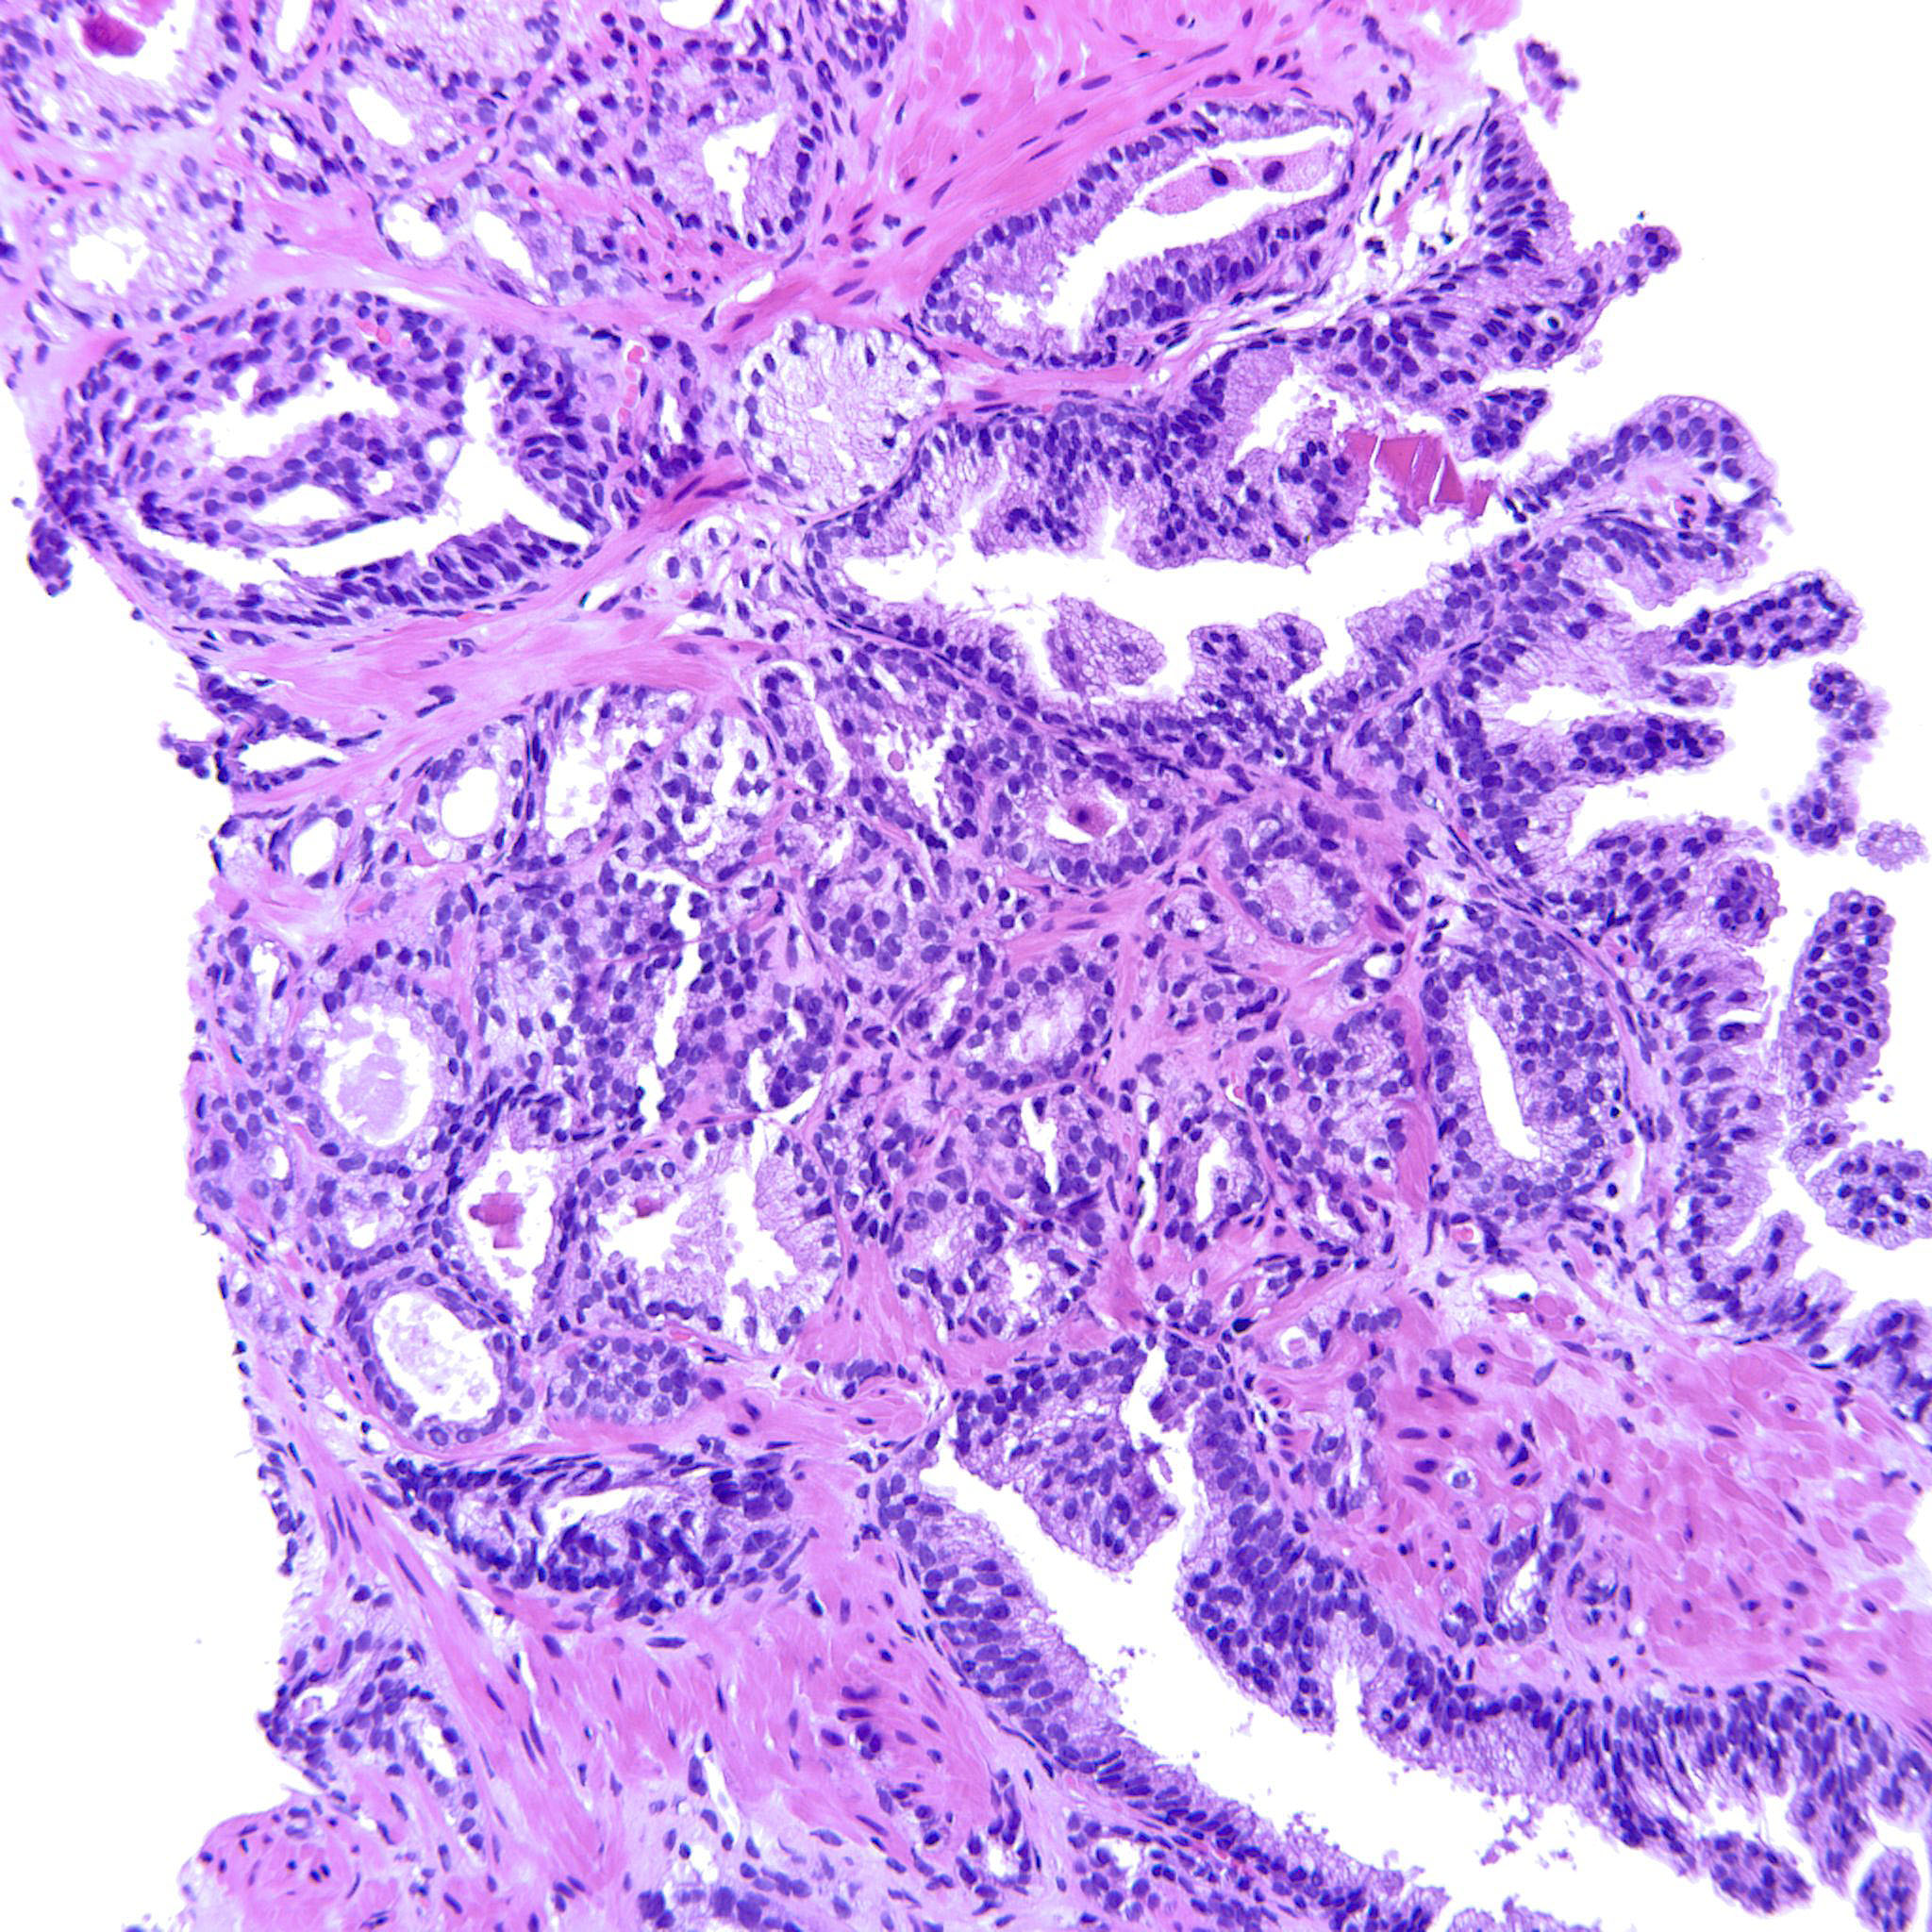

Prostate cancer grading

Case ID: 752